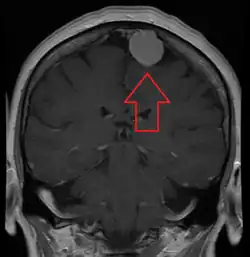

![]() | |

An MRI of the brain, demonstrating the appearance of a meningioma | |

Meningiomas are visualized readily with contrast CT, MRI with gadolinium,[23] and arteriography, all attributed to the fact that meningiomas are extra-axial and vascularized. CSF protein levels are usually found to be elevated when lumbar puncture is used to obtain spinal fluid. On T1-weighted contrast-enhanced MRI, they may show a typical dural tail sign absent in some rare forms of meningiomas.[18]